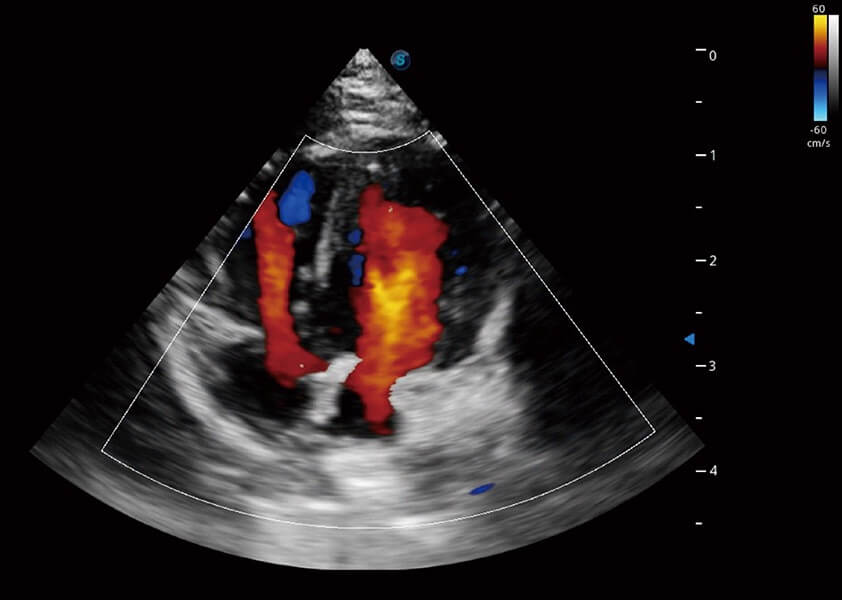

ProPet 60 作为一款高端台式动物超声设备,为动物医生的日常诊断提供了一系列贴合动物临床需求、解决临床实际问题的高级成像功能。凭借全系列高清探头,满足医生对腹部、心脏、生殖、浅表、肌骨等成像的所有需求,切实帮助您提升检查效率,提高诊断信心。

动物是人类最亲密的朋友和最值得信赖的伙伴。米兰官方网站也一直致力于探索动物专用的超声影像解决方案。 全新推出的ProPet系列,是米兰官方网站在动物超声影像智能化、专业化、精准化的一次跨越式革新。动物不能用言语来表述自己的不适,通过超声影像,ProPet系列搭建了动物医生与不同物种沟通的“桥梁”,为动物医生注入了“治愈之力”。